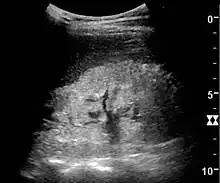

Kidney ultrasonography is useful for diagnostic and prognostic purposes in chronic kidney disease. Whether the underlying pathologic change is glomerular sclerosis, tubular atrophy, interstitial fibrosis, or inflammation, the result is often increased echogenicity of the cortex. The echogenicity of the kidney should be related to the echogenicity of either the liver or the spleen (Figure 22 and Figure 23). Moreover, decreased kidney size and cortical thinning are also often seen and especially when disease progresses (Figure 24 and Figure 25). However, kidney size correlates to height, and short persons tend to have small kidneys; thus, kidney size as the only parameter is not reliable.[54]

Chronic renal disease caused by glomerulonephritis with increased echogenicity and reduced cortical thickness. Measurement of kidney length on the US image is illustrated by '+' and a dashed line.[54]